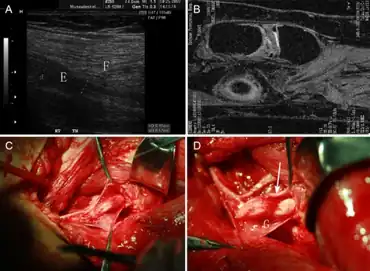

| Micrograph of a nerve with a decrease in myelinated nerve fibres (pink) and an abnormal increase in fibrous tissue (yellow), as may be seen in nerve injuries. HPS stain. | |